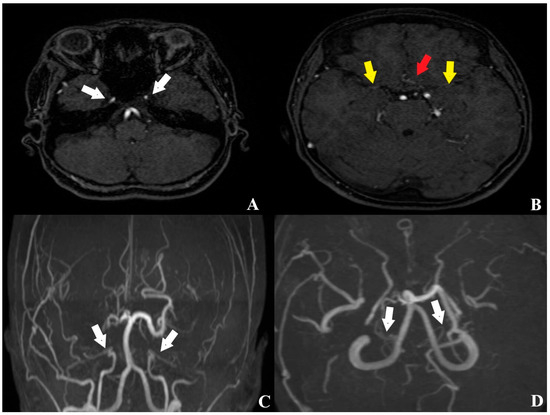

According to the history obtained from her husband, the patient had experienced a hemorrhagic stroke 15 years earlier, at which time MR angiography had confirmed the diagnosis of MMD, and she underwent multiple burr hole surgery (Figure 3 and Figure 4).

Figure 3. Pre-revascularization MR angiography obtained 15 years earlier ((A,B) axial planes; (C,D) 3D reconstructions). White arrow: decreased caliber of the internal carotid artery (ICA); yellow arrow: attenuated caliber of the middle cerebral artery (MCA); red arrow: reduced diameter of the anterior cerebral artery (ACA).